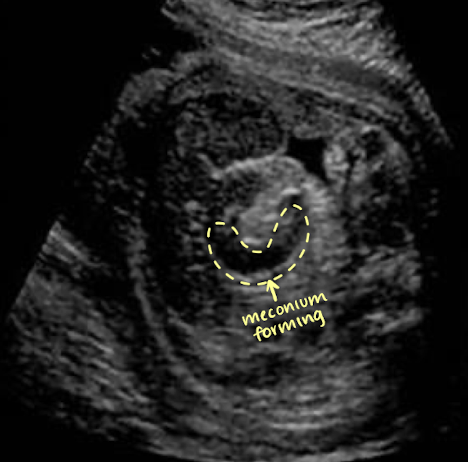

large bowel

seen after 22w (can discern between small and large)

more peripherally than small bowel

hypoechoic tubular structure (meconium)

meconium=baby stool

well-defined walls

haustral folds appear as thin linear echoes within lumen